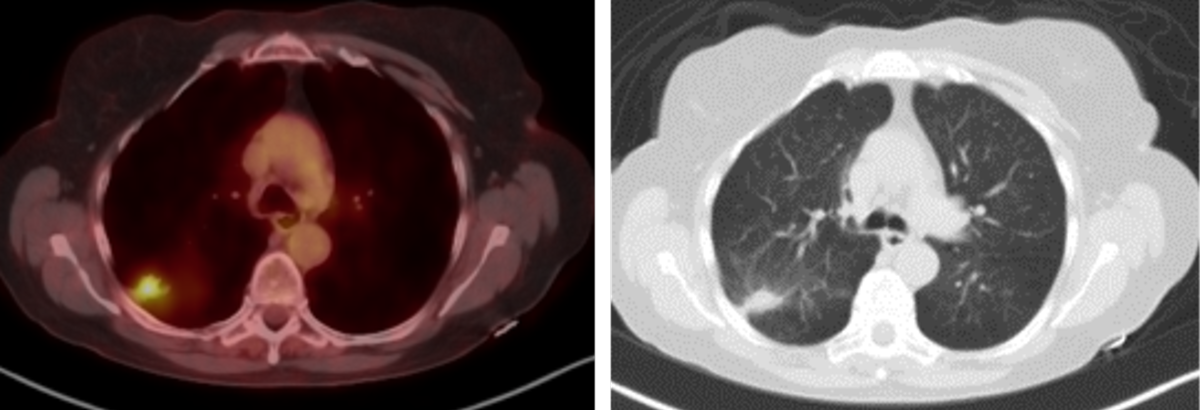

2018 study – Below threshold SUV. SUV max 2.2

2020 study – Biopsy-proven adenocarcinoma. SUV max 5.4